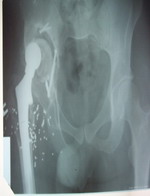

Հիվանդը գանգատվում է աջ կոնք-ազդրային հոդի շրջանի ցավոտությունից և աջ ստորին վերջույթի հարաբերական կարճացումից: Հիվանդիաջ կոնքազդրային հոդում շարժումները ամբողջ ծավալով են, սակայն ցավոտ: Հիվանդի աջ ոտքը 7սմ-ով կարճ է ձախից (նկ. 1): Հիվանդըքայլում է կաղալով աջ ոտքից, մեկ հենակով` բռնած աջ կողմում:

նկ. 1. Հաշվի առնելով հիվանդի գանգատները և աջ ստորին վերջույթի համեմատական կարճացումը` որոշում էկայացվում կատարել ռևիզիոն արթրոպլաստիկա, փոխելով 2 կոմպոնենտները տեղադրելով նոր էնդոպրոթեզիրենց ճիշտ անատոմիական դիրքում: